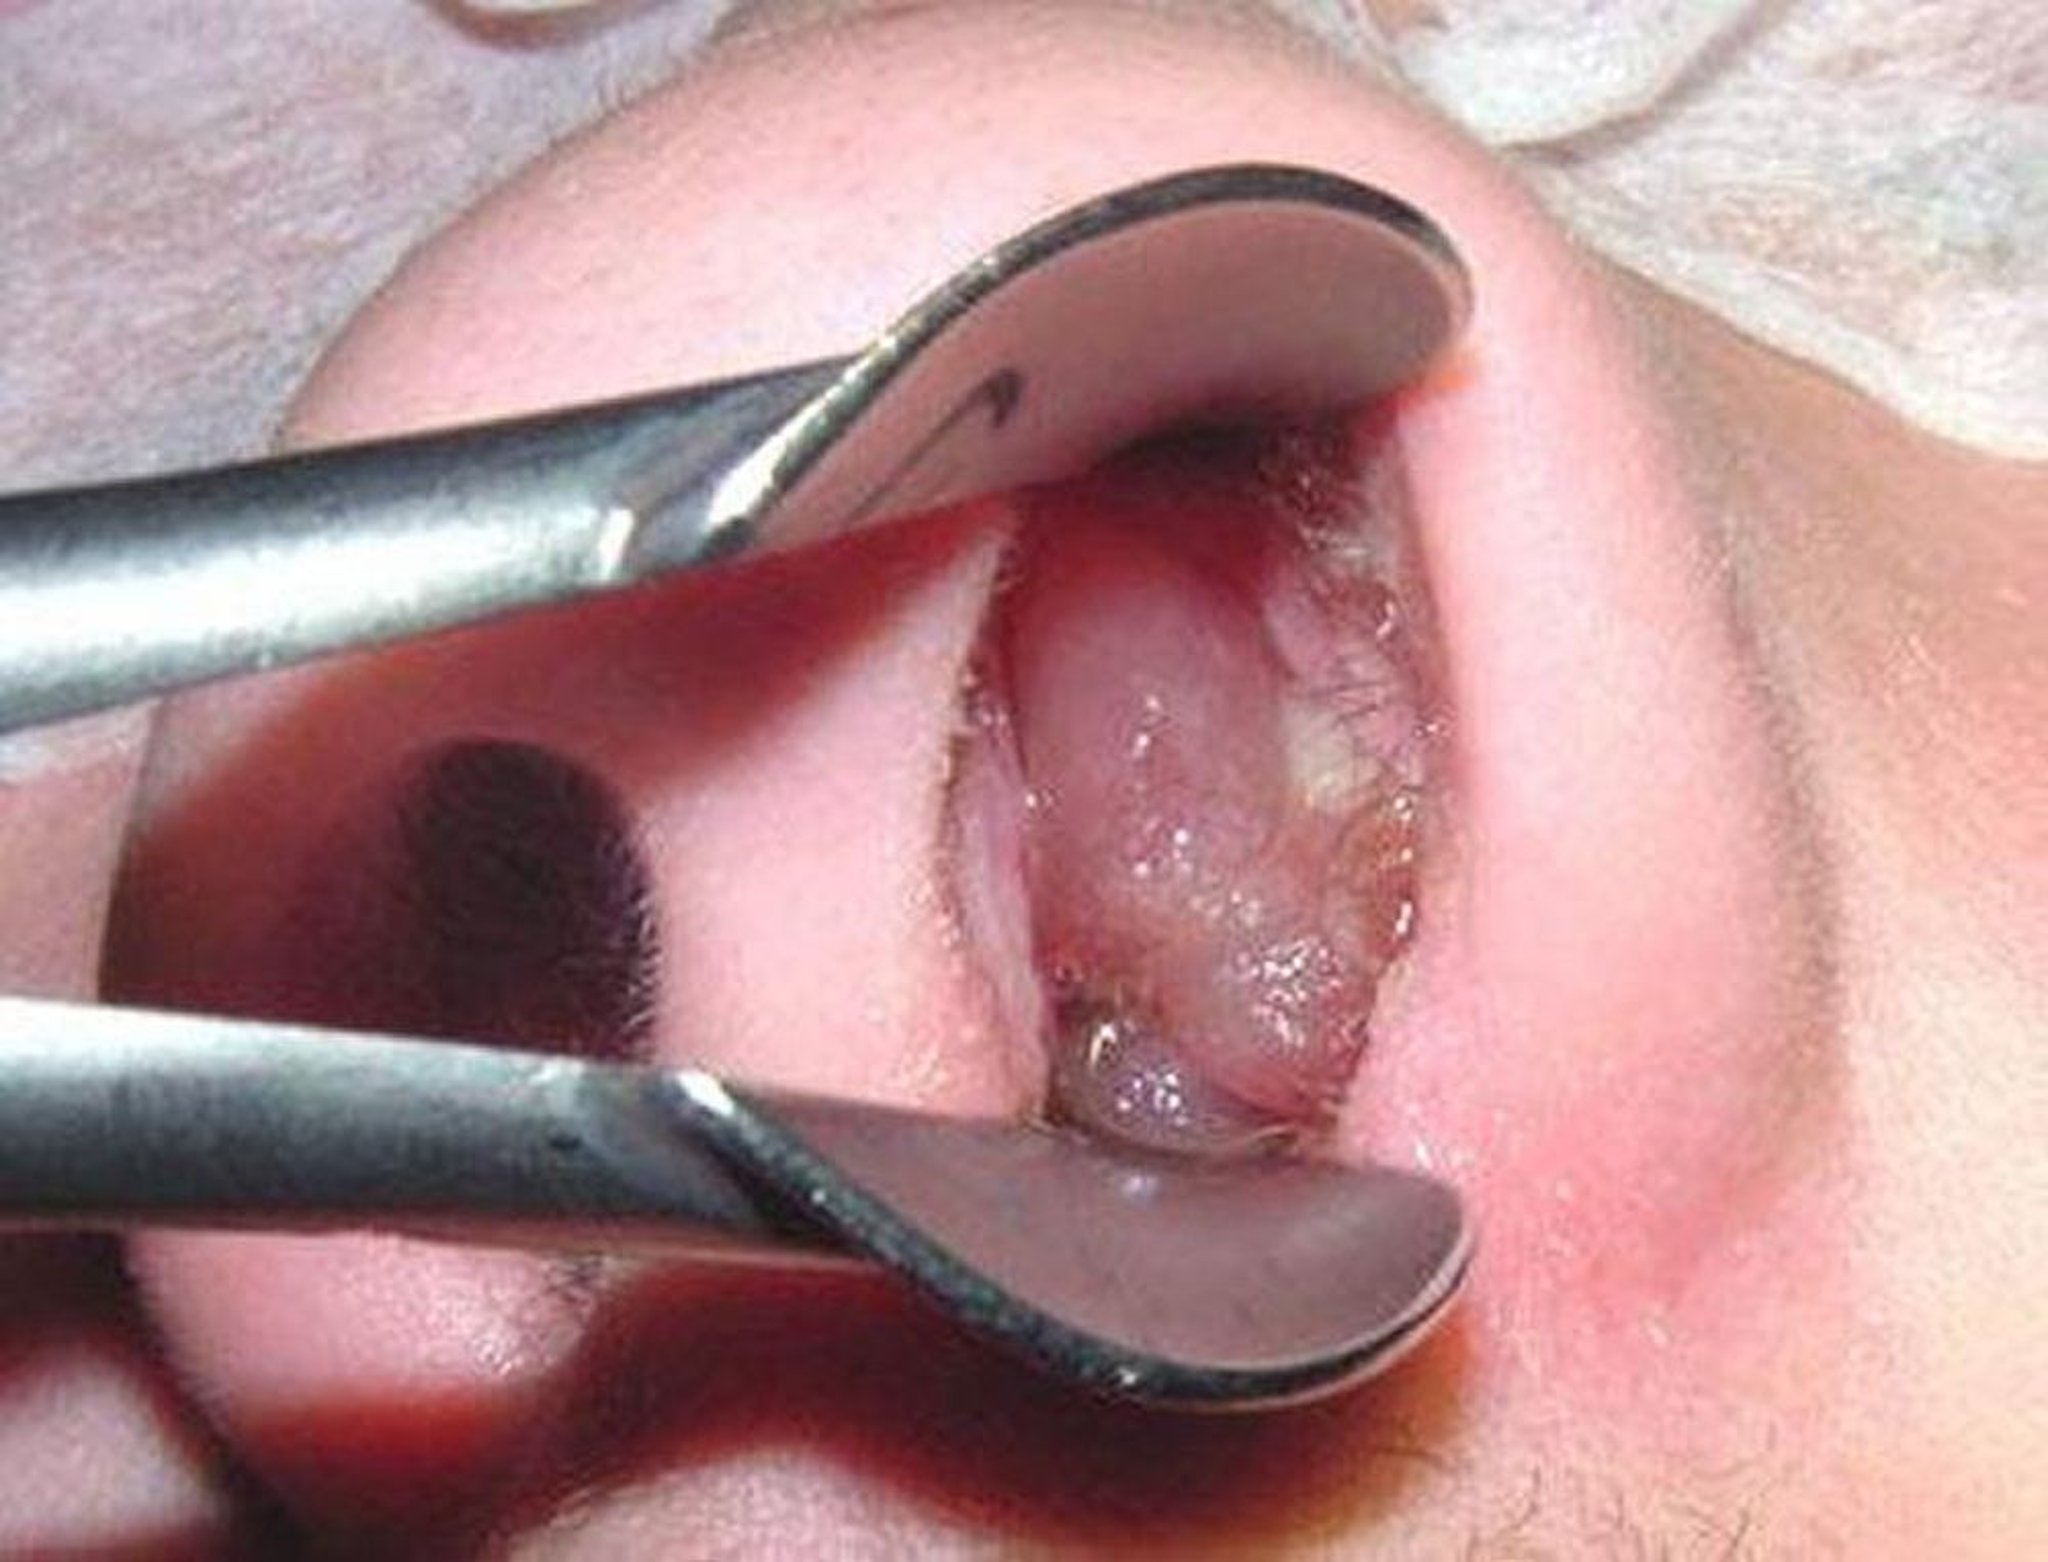

Un polype nasal mature peut ressembler à un grain de raisin sans pépins et sans peau.

Photo fournie par le Dr Bechara Ghorayeb.